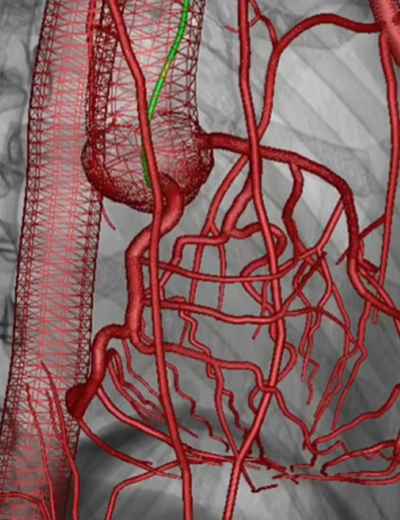

Contrast Agent Control

• Real-time vascular roadmap creation

• Enhanced catheter navigation

• Dynamic fluoroscopy integration

• Training for precision & workflow familiarity